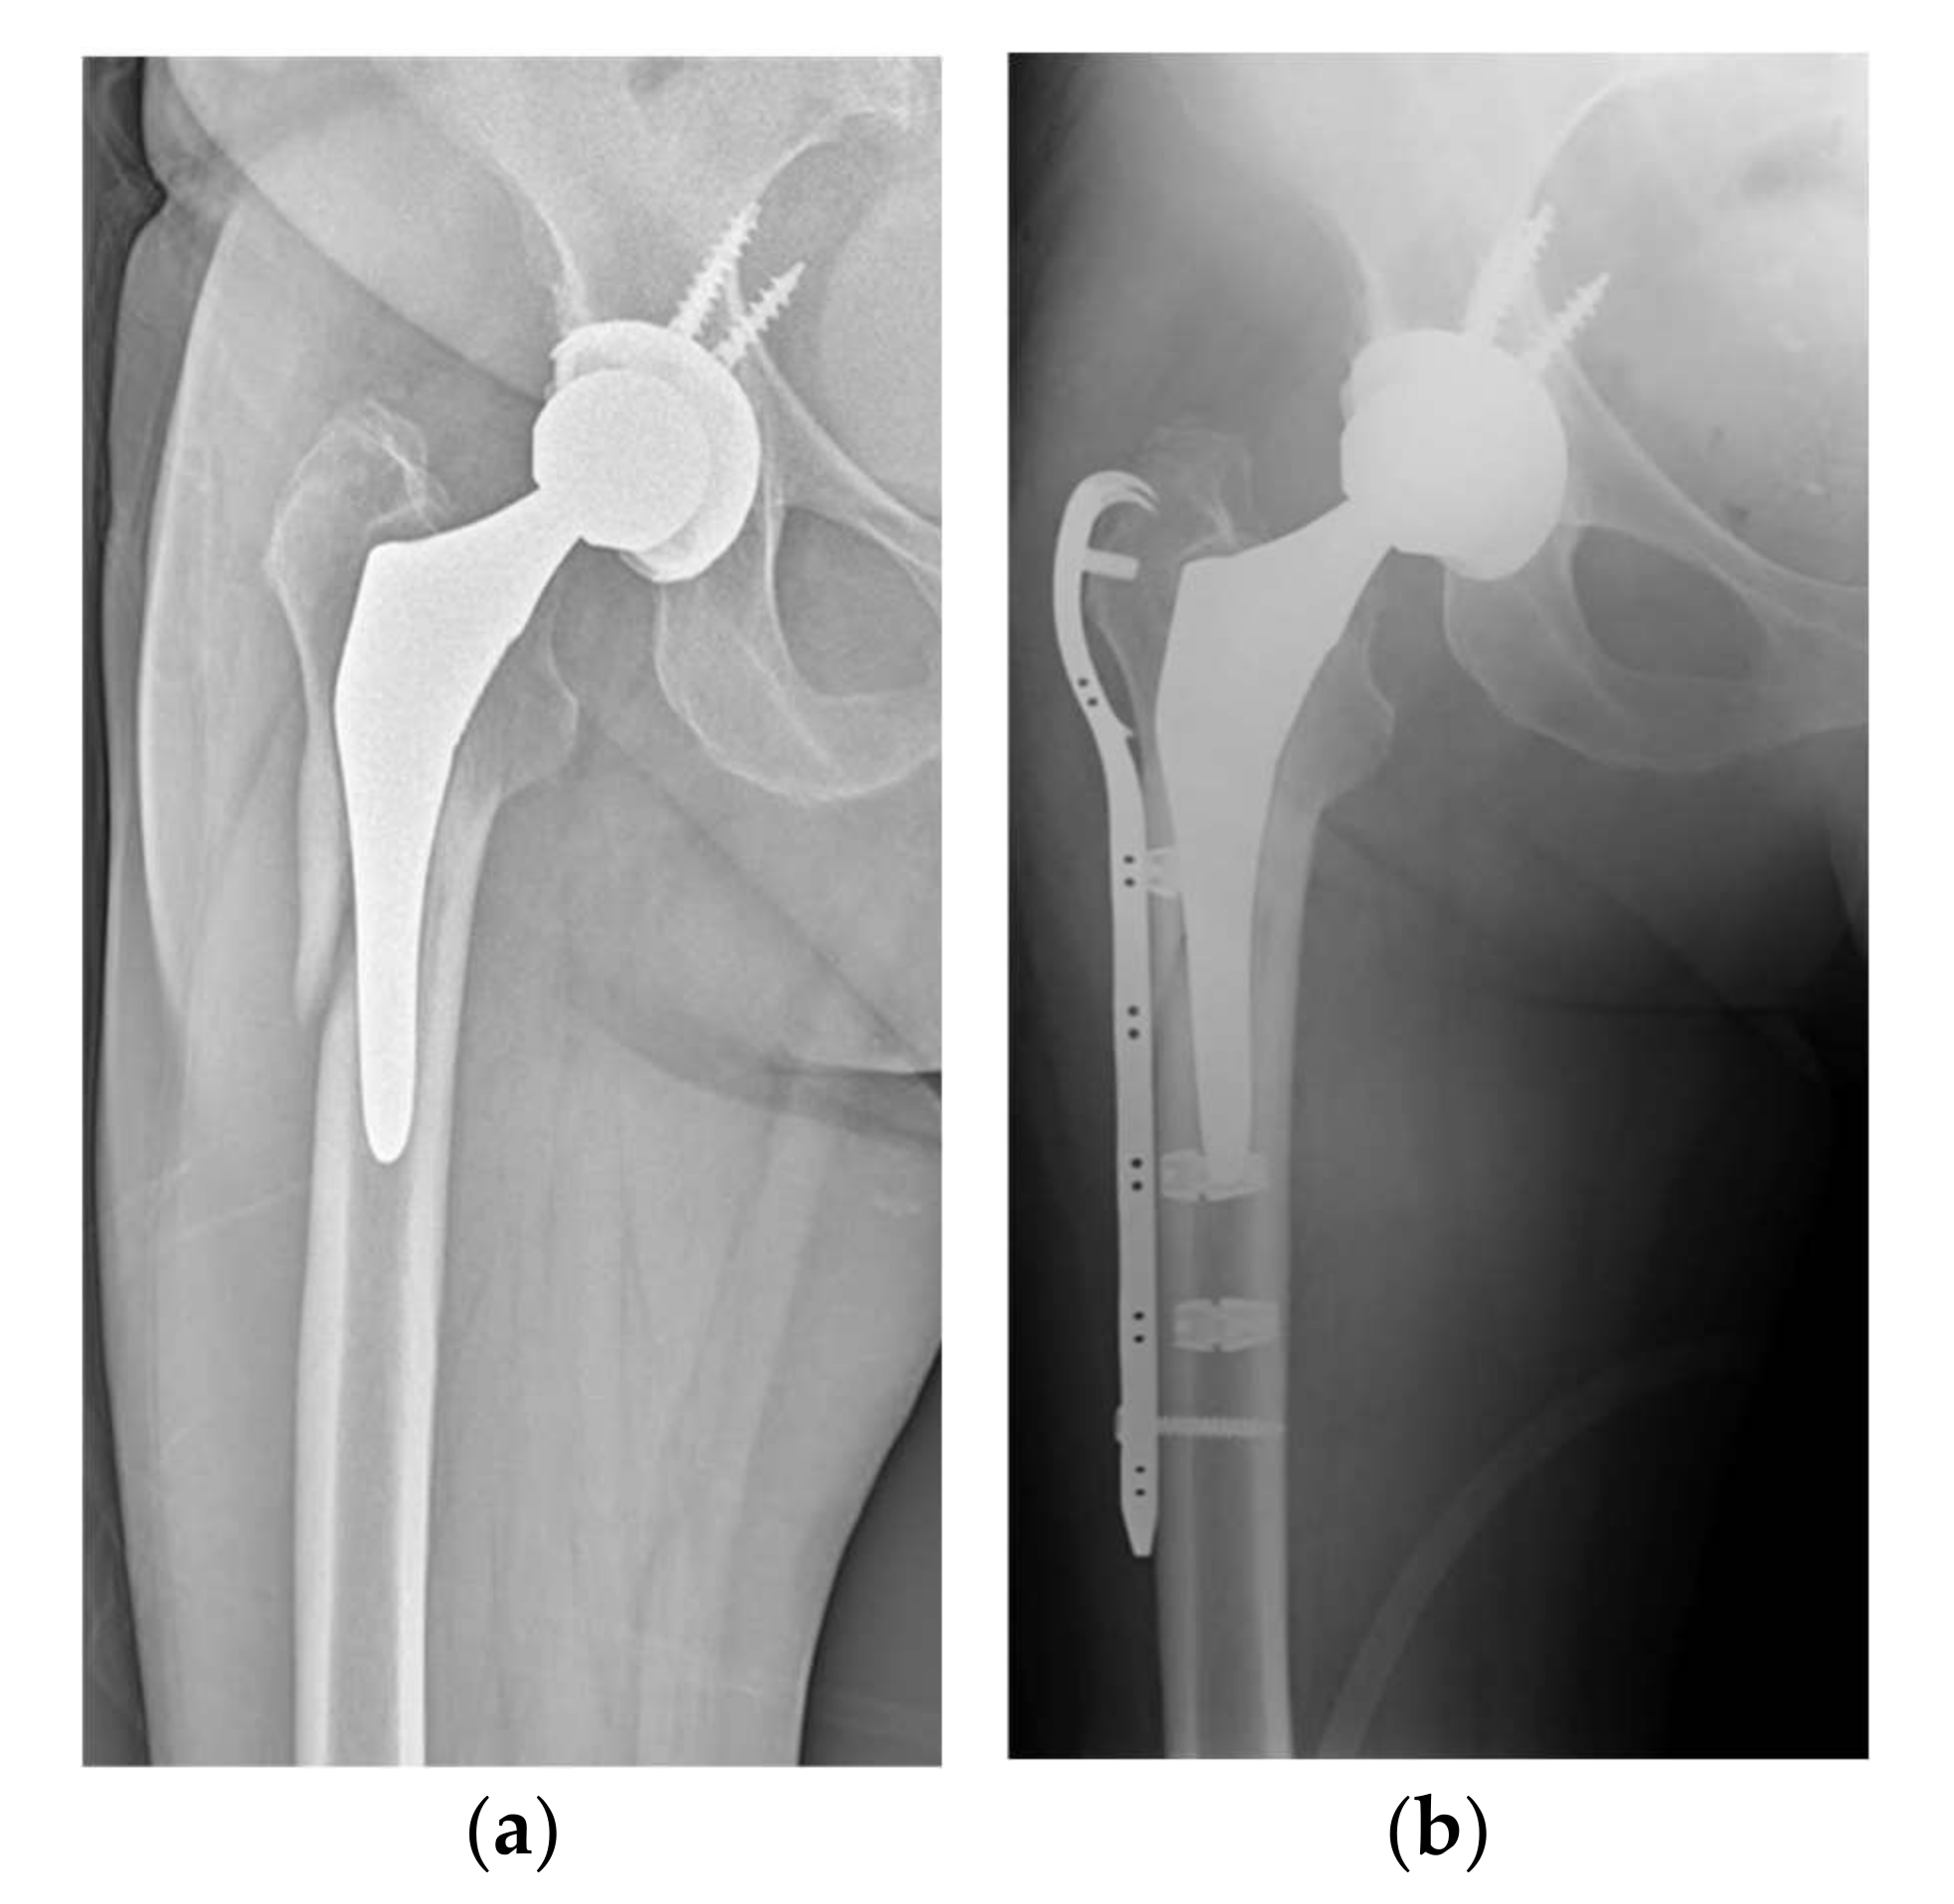

Metallic versus Non-Metallic Cerclage Cables System in Periprosthetic Hip Fracture Treatment: Single-Institution Experience at a Minimum 1-Year Follow-Up

2. Materials and Methods

3. Results